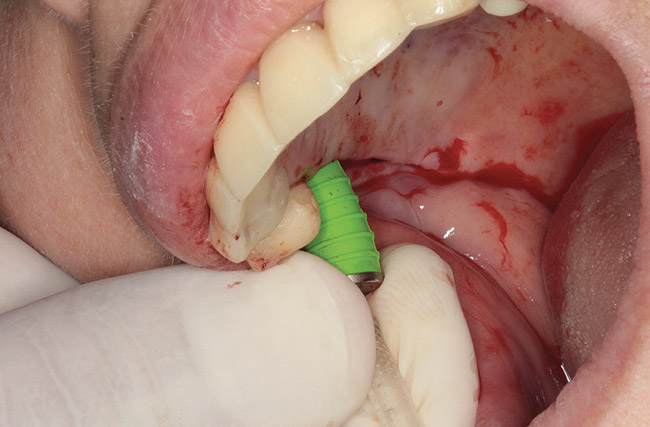

Fig 11. Dental implants are inserted through the crestal osteotomy preparation.

Figure 11